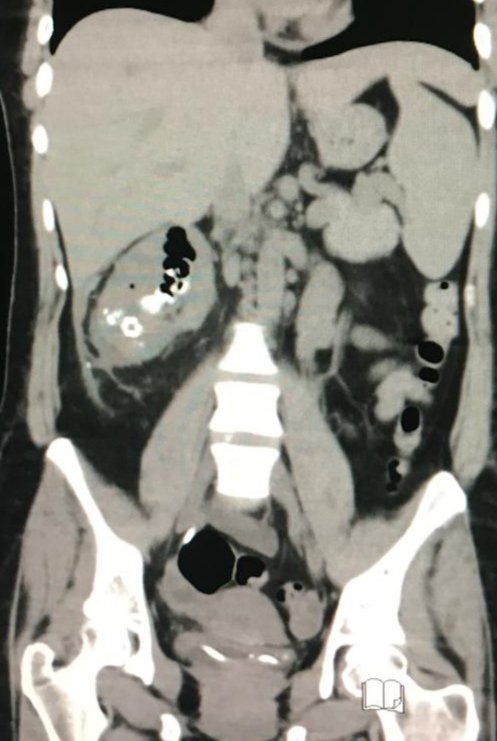

Another posterior tumor for lap partial nephrectomy! Is this a signal to try retroperitoneal approach?

#UroSoMe#UroSoMeBrasil#KidneyCancer#laparoscopypic.twitter.com/6tsHwiVLxQ -